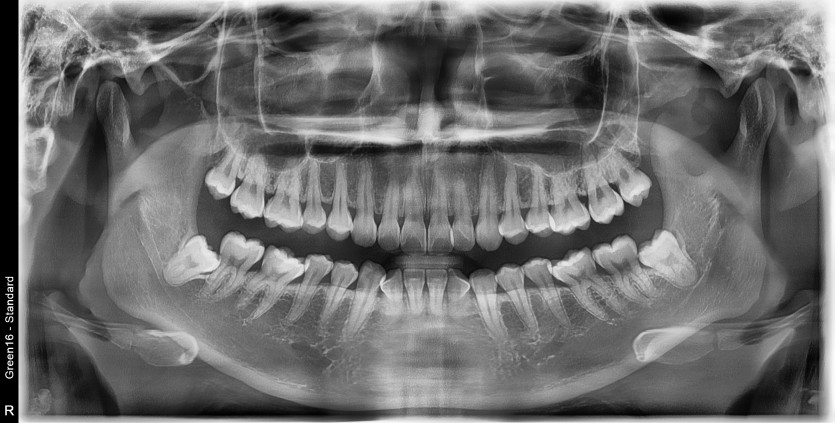

#28,38 사랑니 발치

구강 외과 전문의가 당일 발치했습니다.